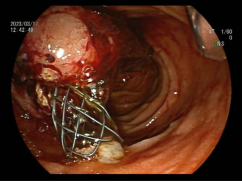

8.内镜下内痔硬化剂及套扎治疗

内镜套扎治疗及硬化治疗 适合I-III期 内痔,包括部分混合痔的微创治疗,疗效显著,与传统外科手术相比,超级微创、费用低、见效快,具有很大优势。

III度内痔 硬化剂及套扎术后